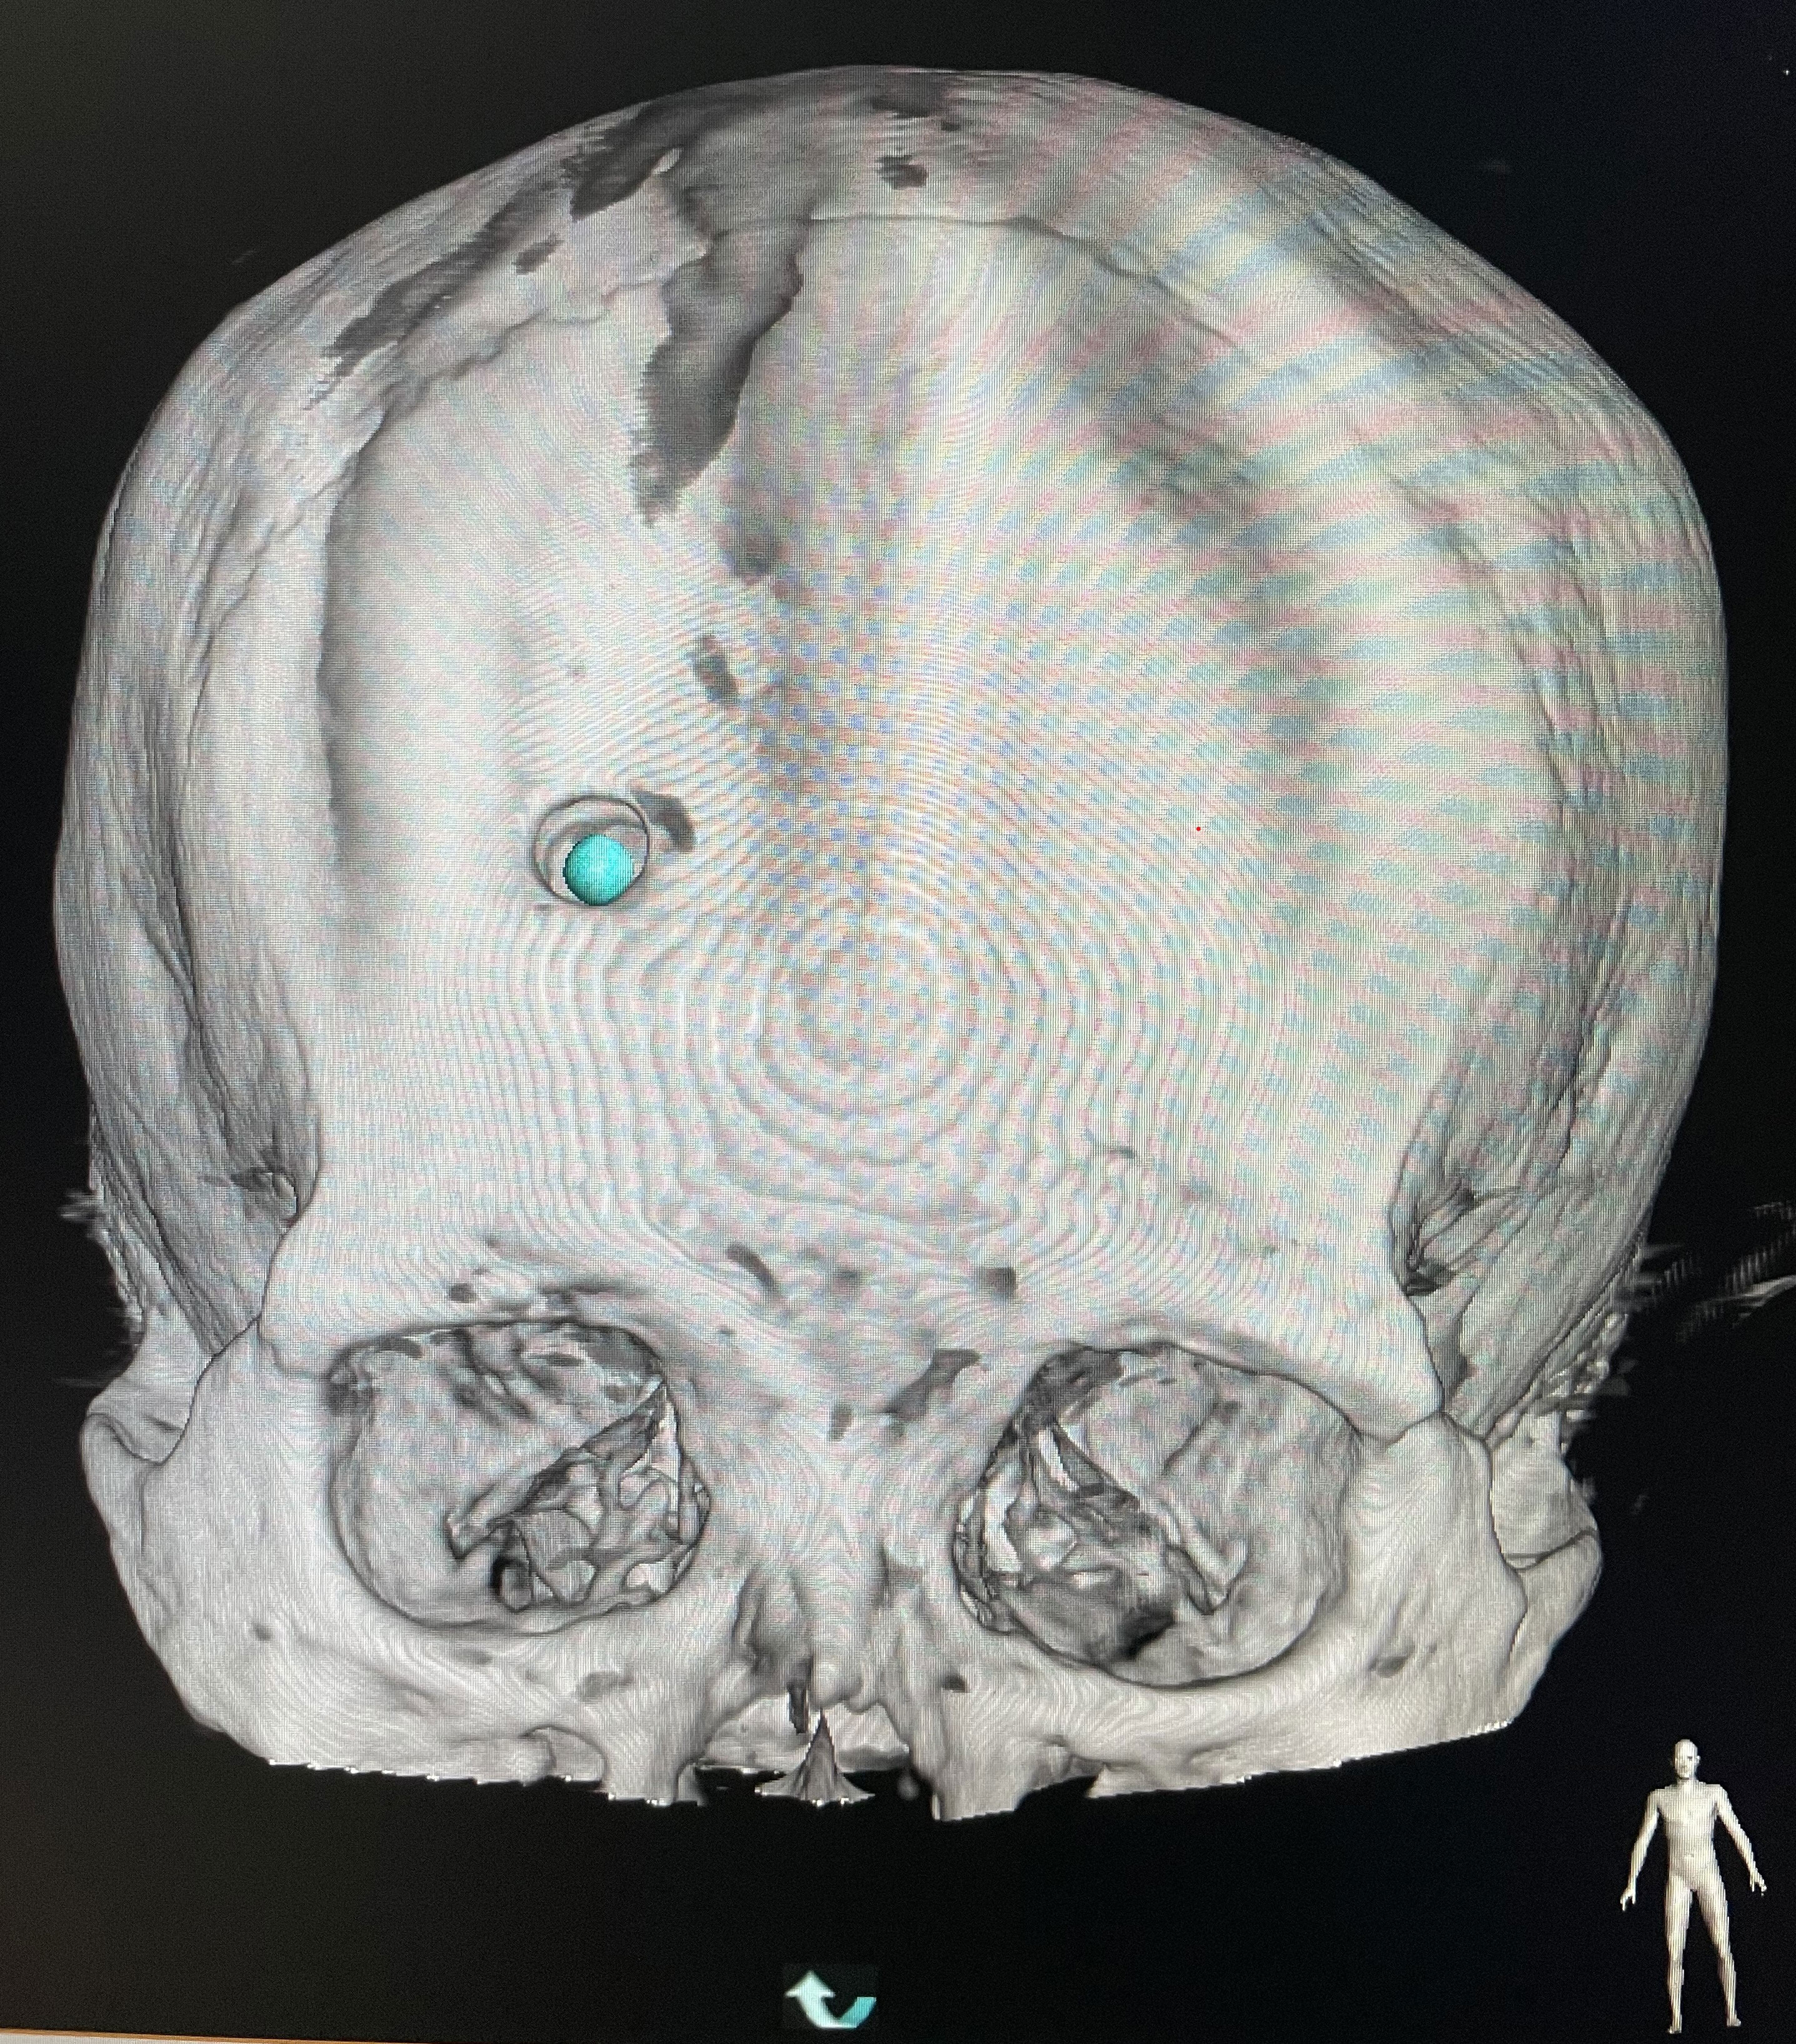

The surgical incision site was marked with a metal object on the forehead, approximately 2 cm from the midline and 3 cm from the orbit on the hematoma side (Figure 2). The priority was to make an incision in the frontal stria and avoid the frontal sinus to prevent cerebrospinal fluid leakage after surgery and ensure an aesthetically pleasing appearance after wound healing. A hole was drilled in the bone at the metal mark (Figure 3). The C-arm CT function of the digital subtraction angiography (DSA) machine was used to collect the original data for processing; display the coronal, sagittal, and axial CT images; mark the center of the hematoma; and set it as the target site for the puncture (Figure 4). The 3D reconstruction of brain tissue was performed using the 3D reconstruction software Xper CT of the DSA machine, and the bone hole displayed in gray scale was adjusted as the puncture point. Subsequently, the 3D stereo image was rotated, overlapping the puncture point and puncture target. The laser emission direction was determined using the principle of “two points and one line,” and the real-time 3D reference image working angle was recorded (Figure 5). The skull was cut along the coinciding point, and the distance between the puncture point and the puncture target was measured as the puncture depth (Figure 6).

A surgical incision was planned on the forehead scalp at the metal marker, with a length of approximately 2 cm. We stuck the bottom of the laser emitter on the FD plate, making the laser emitted from it perpendicular to the FD plate, then moved the laser emitter, and focused the cross-laser on the puncture point. Consequently, the direction of laser emission passed through the puncture point and puncture target simultaneously, which was determined as the puncture direction, and the puncture needle was held at the puncture point to conduct the puncture. During puncture, the laser focus was continuously placed at the center of the needle tail. At this time, the puncture of the trocar was continuously directed toward the center of the hematoma. Puncture depth was defined as the distance from the puncture point to the puncture target measured before surgery (Figure 8). Dark red blood flowed out through the drainage tube after the tube core was pulled out.